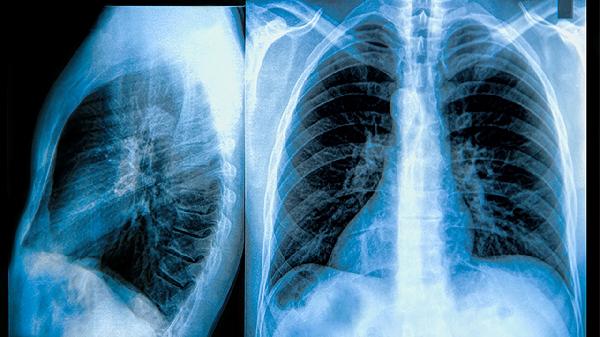

玻璃体肺部结节可能是指肺部影像学检查中发现的一种具有玻璃样影像特征的肺结节,原因可能包括炎症、感染、自身免疫疾病及早期肺癌等。需要根据具体情况进行原因排查并采取针对性的治疗措施。

肺癌:虽然玻璃体结节不一定是癌症,但早期肺癌常以此为表现。低剂量螺旋CT筛查能提高早期发现率,肺部影像显示可疑时可选择穿刺活检或手术切除。

影像学随访:定期通过CT检查观察结节变化。若结节发现后增大、有不规则边缘或磨玻璃影表现,需要进一步检查。